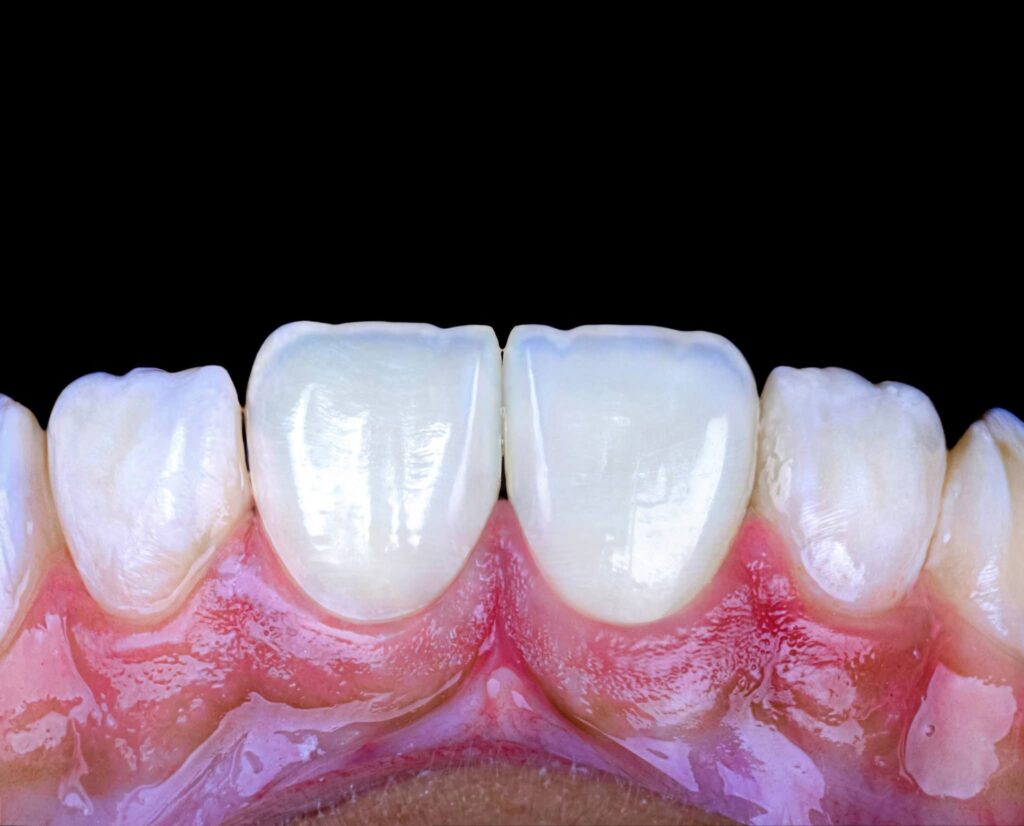

Symmetry and proportionality are fundamental principles in aesthetic dentistry, particularly in direct composite veneers, where the clinician acts simultaneously as a scientist and an artist. Successful veneers are not determined only by color and shape, but by the harmony between teeth, gingiva, lips, and face.

Symmetry refers to the mirror relationship between the right and left sides, especially the maxillary central incisors. Absolute symmetry is not always natural; therefore, perceived symmetry is more important than mathematical symmetry. Small differences in line angles, embrasures, and incisal edges can be used intentionally to create a natural appearance.

Proportionality relates to the width-to-length ratio and the relationship between anterior teeth. The ideal width/length ratio for central incisors is approximately 75–80%, and the apparent width proportion between anterior teeth often follows the golden proportion (~62%), although modern aesthetic dentistry prefers the concept of Recurring Esthetic Dental (RED) proportion for more natural results.

Direct composite veneers require a balance between mathematical proportions and artistic perception. The most aesthetic result is achieved not by perfect symmetry, but by natural, harmonious asymmetry combined with correct proportions.